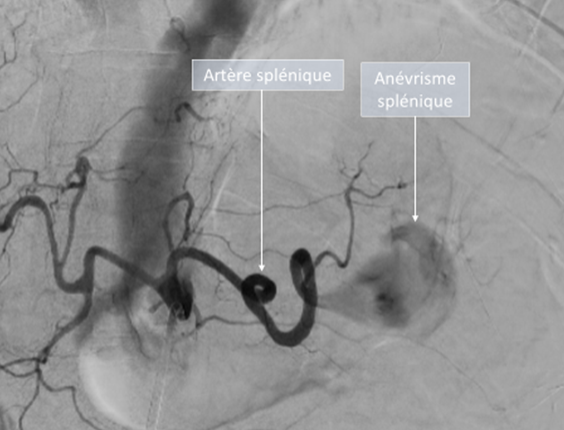

Elle implique, après la réalisation d’une anesthésie locale, la mise en place d’un petit tuyau dans une artère du poignet ou du pli de l’aine qui permettra d’insérer de façon indolore une sonde (cathéter) afin de naviguer dans vos artères. Le radiologue réalise ensuite une exploration de l’artère porteuse de l’anévrisme, sous contrôle radiographique.

Le radiologue procède ensuite à l’embolisation par injection d’agents destinés à occlure les vaisseaux. Les agents utilisés diffèrent selon la lésion et la configuration anatomique des vaisseaux (spires, plugs, colle, …). Dans certains cas particuliers, le radiologue peut être amené à positionner un « ressort » (stent) permettant d’exclure l’anévrisme tout en préservant la bonne perméabilité de l’artère qui le porte.